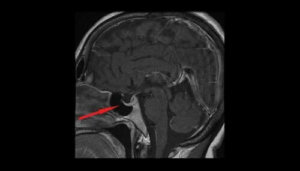

De mest relevante testene som hjelper til med å bekrefte diagnosen, er synsfeltet og CT- og hjerner MR.